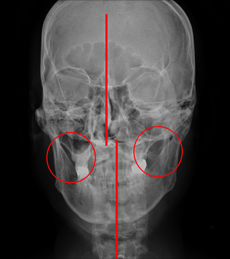

- X-RAY

- 턱뼈 뿐만 아니라 전신의 구조적인

문제를 확인합니다.

치료 전후 사례

-

- 턱관절장애로 코와 입술이 사선으로 틀어진 환자로 교정치료와

한약 복용 후 틀어져 있던 코와 입술, 턱선이 균형을 이룸

- 턱관절장애로 코와 입술이 사선으로 틀어진 환자로 교정치료와